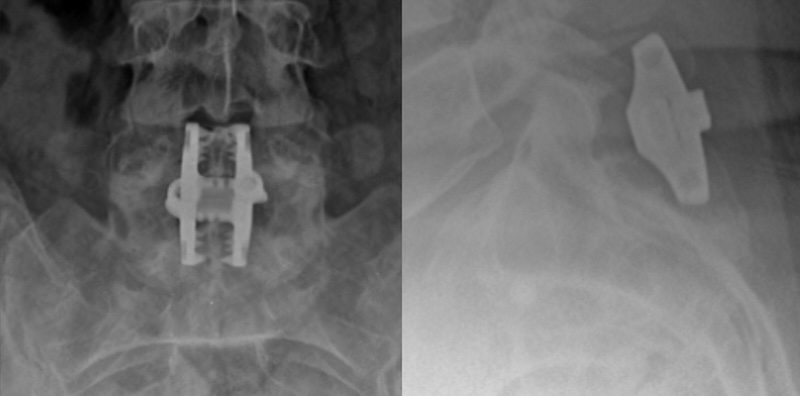

InSpan Interspinous Clamp Fixation

The Inspan Spinous Process Plate System by NANISX (Company of KIC Ventrures) is an interspinous process stabilization clamp composed of titanium with a contour that allows it to fit snugly up against the lamina. It features two interconnected plates that compress together against the spinous process to produce stabilization across the two vertebrae.

• Spike and tooth fixation on the endplates for fixation to spinous process